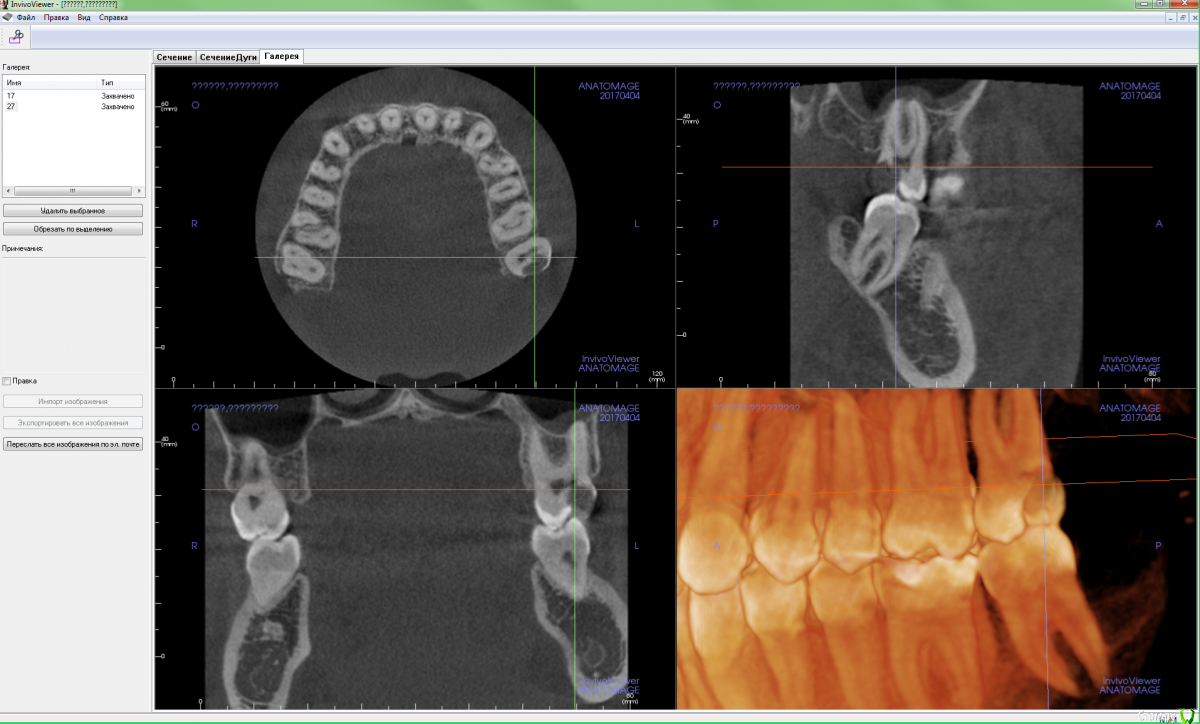

Xealer Опубликовано 20 апреля, 2017 Поделиться Опубликовано 20 апреля, 2017 (изменено) Здравствуйте! Меня зовут Руслан, мне 31 год.Меня 2 месяца назад стал беспокоить зуб 27.Моя цель: вылечить зуб 27 с минимальным вмешательством, сохранить нервы в пульпе. После этого вылечить зуб 17.Предыстория в спойлере:удалено администраторомТеперь зуб частично разрушен, видимо пломба отвалилась. Диагноз - пульпит.До этого боль была ноющая, сильно не беспокоила.Вчера полчаса болел сильно, сейчас снова утихла.Вопрос 1: Означает ли это, что пломба была установлена плохо?Стал ходить по разным стоматологам, с хорошей репутацией(подробности в спойлере) удалено администраторомудалено администраторомбыл только на консультациях: удалено администратором Сказал, что нужно сделать 3d томографию всех зубов и ставить коронку на 27. Цена 10 тыс руб. удалено администратором(стаж более 25 лет, высокая репутация в интернете): Посмотрел 3d томографию, сказал, что лучше поставить коронку, но можно поставить пломбу! Когда, я спросил про материалы для коронки, сказал, что можно поставить: - металлокерамическую коронку (CoCr) - титан Стал немного путаться в цене. Отправил к стоматологу-терапевту удалено администратором, на первоначальное лечение перед установкой коронки. Цена 12 - 15 тыс руб. Про зуб 17 сказал, что коронку ставить не надо, можно поставить пломбу.удалено администратором удалено администраторомРассказал про лечение подробнее, чем остальные, показал фотографию разрушенного зуба. Сделал 3d томографию. Назвал высокие цены, сославшись на то, что в других стоматогиях некачественные материалы, а у них качественные немецкие материалы. Цена 34-50 тыс руб включает: Сумма в руб Изготовление культевой вкладки разборной либо за 8000, либо за 15000 Изготовление металлокерамической коронки (CoCr) - Некая стандартная цена 14000 (видимо стандарная цена в моём случае не использовалась, была на бланке) - Литьевой метод 20000 - Фрезерный метод 30000 и т д Про зуб 17 сказал, что коронку ставить надо, и ставить пломбу на него неграмотно с медицинской точки зрения, так как стенка до пульпы всего 1 мм. Остальные вопросы:2. Могут ли такие цены, которые мне предложили в удалено администратором за "качественные немецкие материалы", быть честными?3. Можно ли поставить пломбу на 27, сохранив пульпу?4. Если ставить коронку на 27, то какой материал выбрать? нужен ли титан?5. Достаточно ли на 17, поставить пломбу?6. Какого стоматолога порекомендуете? Во вложении я сделал скриншот срезов 27 и 17, где расстояние до пульпы минимально. Если надо могу выложить весь файл с 3d томографией. Изменено 25 апреля, 2017 пользователем red_butler Ссылка на комментарий

Pan Опубликовано 22 апреля, 2017 Поделиться Опубликовано 22 апреля, 2017 Ваш зуб требует эндодонтического лечения, требует ли Ваш зуб ортопедического лечения( коронки) трудно оценить по представленным снимкам. Даже если учитывать утрату тканей для эндо доступа, следует оценить оставшиеся ткани для возможной реставрации зуба без применения ортопедической конструкции. 1 Ссылка на комментарий

Xealer Опубликовано 8 ноября, 2020 Автор Поделиться Опубликовано 8 ноября, 2020 Посмотрите пожалуйста изображения с новой компьютерной томографией зуба 27.Не появился ли периодондит?https://gitlab.com/sputn/health_dataЗуб(если его ещё можно так назвать) не беспокоит. Ссылка на комментарий

Xealer Опубликовано 9 ноября, 2020 Автор Поделиться Опубликовано 9 ноября, 2020 И нужно ли переделывать каналы в зубе и заполнять пустоты в них? Ссылка на комментарий